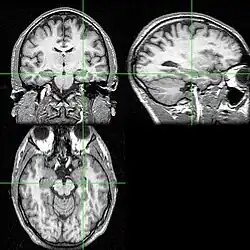

Diversos cortes de ressonância magnética com a localização do hipocampo (cruzamento das linhas verdes). -